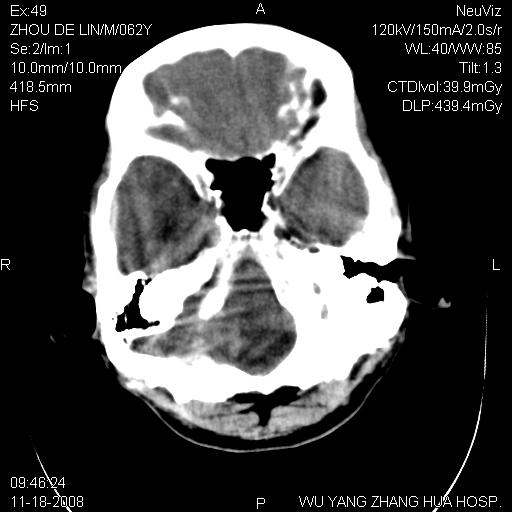

患者近段时间偶有头晕,无其他不适。既往有糖尿病病史。

小脑中线区见一类圆形混杂密度影,四脑室受压变形,其后方见一边界清楚的囊性低密度影,幕上脑室扩张。小脑中线区肿瘤,儿童多见于髓母细胞瘤,成人多见于胶质瘤。

诊断:小脑胶质瘤可能性大。建议增强扫描

小脑囊实性占位病变、脑室系统积水扩张、脑肿胀。

小脑囊实性占位病变、脑室系统积水扩张,建议增强

诊断:小脑胶质瘤可能性大。建议增强扫描。支持!

1)小脑蚓部(偏左侧)占位性病变;不排除转移瘤可能。建议行进一步检查。2)脑积水。